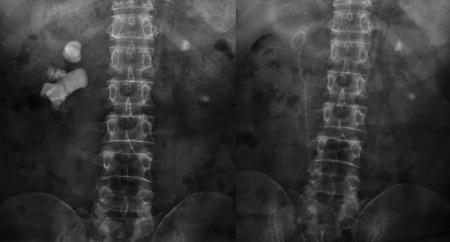

宋先生术前与第二次术后的结石对比

又进行了20多次体外碎石后,肾结石非但没打掉,反而长到了骇人的8公分:X光片里面形似一颗“老姜”,几乎塞满了右肾内的大小通道。

“泌尿道梗阻;右肾多发结石、中度扩张积水;左肾结石伴左肾积水,左肾缩小。”医院的检查结果显示,结石充满了宋先生的右肾,右肾功能受结石和积水的影响,仅剩4成左右,而左肾则出现了可怕的肾萎缩。而这些正是在宋先生接受了惊人的100多次体外冲击波碎石,累计花掉20多万元后,付出的沉重代价。

“人的肾脏约长10-12厘米,普通人两、三厘米的结石,就算比较大的了,而宋先生的肾结石一年多时间,就在肾脏内迅速长到8公分。如此惊人的生长速度,在临床上十分罕见。”宋先生的主刀专家、四川结石病医院泌尿一科易成然主任介绍。

在经历了两次微创经皮肾镜碎石取石手术后,宋先生右肾内的巨大结石被粉碎并清除,解除了尿路的梗阻,肾脏的积水随之消退。目前,宋先生即将康复出院。